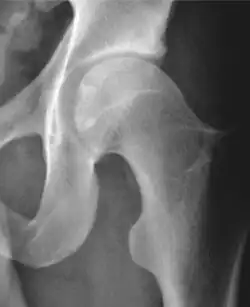

Projectional radiography ("X-ray") is often considered first line for FAI.[10] Anterior-posterior pelvis and a lateral image of the hip in question should be attained.[10] A 45-degree Dunn view is also recommended.[10][19]

| Measurement | Image | Target | Normal value |

|---|---|---|---|

| Center-edge angle of Wiberg | ![]() |

The superior-lateral coverage of the femoral head. | |

| Crossing ratio |

|

Percentage of acetabular walls crossing. Normal acetabulum is oriented in anteversion. Its value ranges from 15 to 20° in the equatorial plane of the acetabulum and decreases gradually towards the acetabular roof, where normal values range from 0 to 5°. Retroversion of the upper part of the acetabulum has been related with pincer type impingement. In radiography the presence of a "crossover sign" is produced when the posterior wall of the acetabulum crosses the anterior wall before reaching the acetabular roof. It is a sign of acetabular retroversion and it has been linked with overcoverage and pincer impingement. Nevertheless, this sign has been described in 6% of the normal population. Therefore, more important than its presence is the percentage of crossing. | <20%

| Alpha angle | ![]() |

Degree of bulging of the femoral head-neck junction: In normal conditions there is a symmetric concave contour at the junction of the femoral head and neck. Loss of this concavity or bone bulging may lead to cam type impingement. The degree of this deformity can be measured by the alpha angle. Although it can be measured in the cross-lateral view, the 45° Dunn view is considered more sensitive and the frog leg view more specific in determining pathologic values. |

| Femoral head-neck offset | ![]() |

Offset of the femoral head with regard to most prominent aspect of the femora neck | >10 mm |

| Offset percentage | Femoral head-neck offset related to femoral head diameter | >0.18

| |

| Tönnis angle |

Slope of the sourcil (the sclerotic weight-bearing portion of the acetabulum) | 0 to 10°

| Caput-sourcil angle[21] |

Superior to the Tönnis angle in cases without joint space narrowing or subluxation.[21] The medial point of the sourcil is at the same height as the most superior point of caput femoris. | −6 to 12°[21]